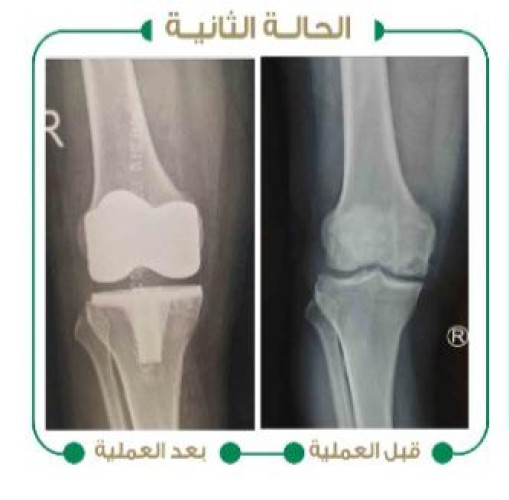

نجح بفضل الله فريق جراحي متخصص في جراحة العظام والمفاصل في مستشفى وادي الدواسر العام، في إجراء عمليتين جراحيتين لمريضين يعانيان من خشونة متقدمة في مفصل الركبة وتقوس شديد مع إرتخاء في الأربطة للركبة وصعوبة في المشي والحركة، حيث تم إجراء عملية تغيير المفصل بمفصل آخر صناعي ومعالجة التقوس، فيما بدأ المريضان مرحلة العلاج الطبيعي والمشي في نفس يوم العملية ولله الحمد.